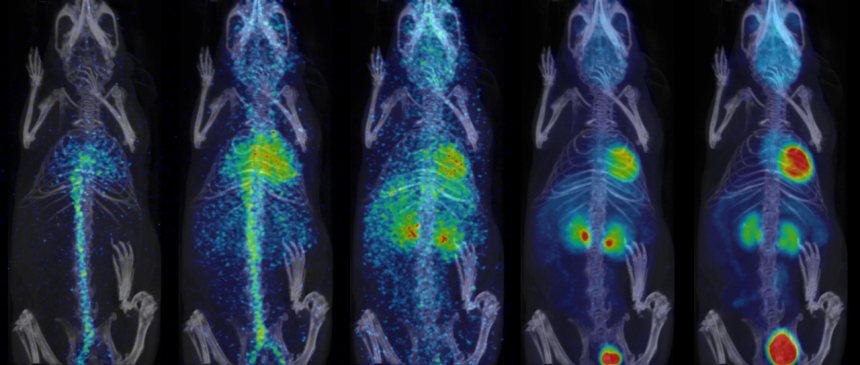

- Fully automated PET/CT stitched protocol, including attenuation correction (AC) map for rats up to 250 mm in length

Fast extended PET/CT imaging for full rat body coverage. Image Credit: Bruker BioSpin Group

Efficient PET scanning

- Data is displayed on the touchscreen as well as in pre-defined single slices for fastest planning of further scans based on tracer biodistribution

- Real-time 3D display of tracer biodistribution during scanning